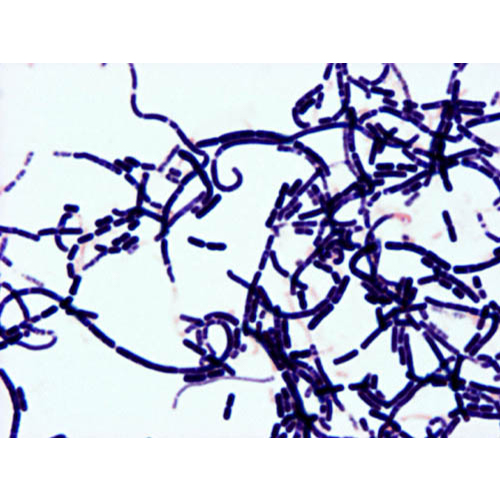

Lactobacillus

Colony Gram stain from an SBA of tiny alpha hemolytic colonies form a vaginal culture

Vaginal Epithelial

Cell with Lactobacillus

Direct Gram stain of a vaginal swab showing a vaginal epithelial cell with Lactobacillus